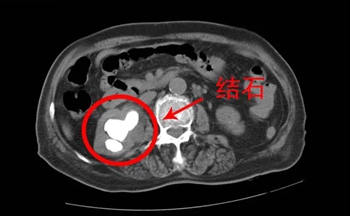

一位87岁老奶奶因反复右腰腹部疼痛到我院泌尿外科就诊,经查患者疼痛1年多伴肾积脓、感染且有多次置双J管史,泌尿外科副主任吴妙锋结合相关检查结果诊断该患者为右肾、右输尿管上段结石并右肾中度积液需尽快手术治疗。

术前CT